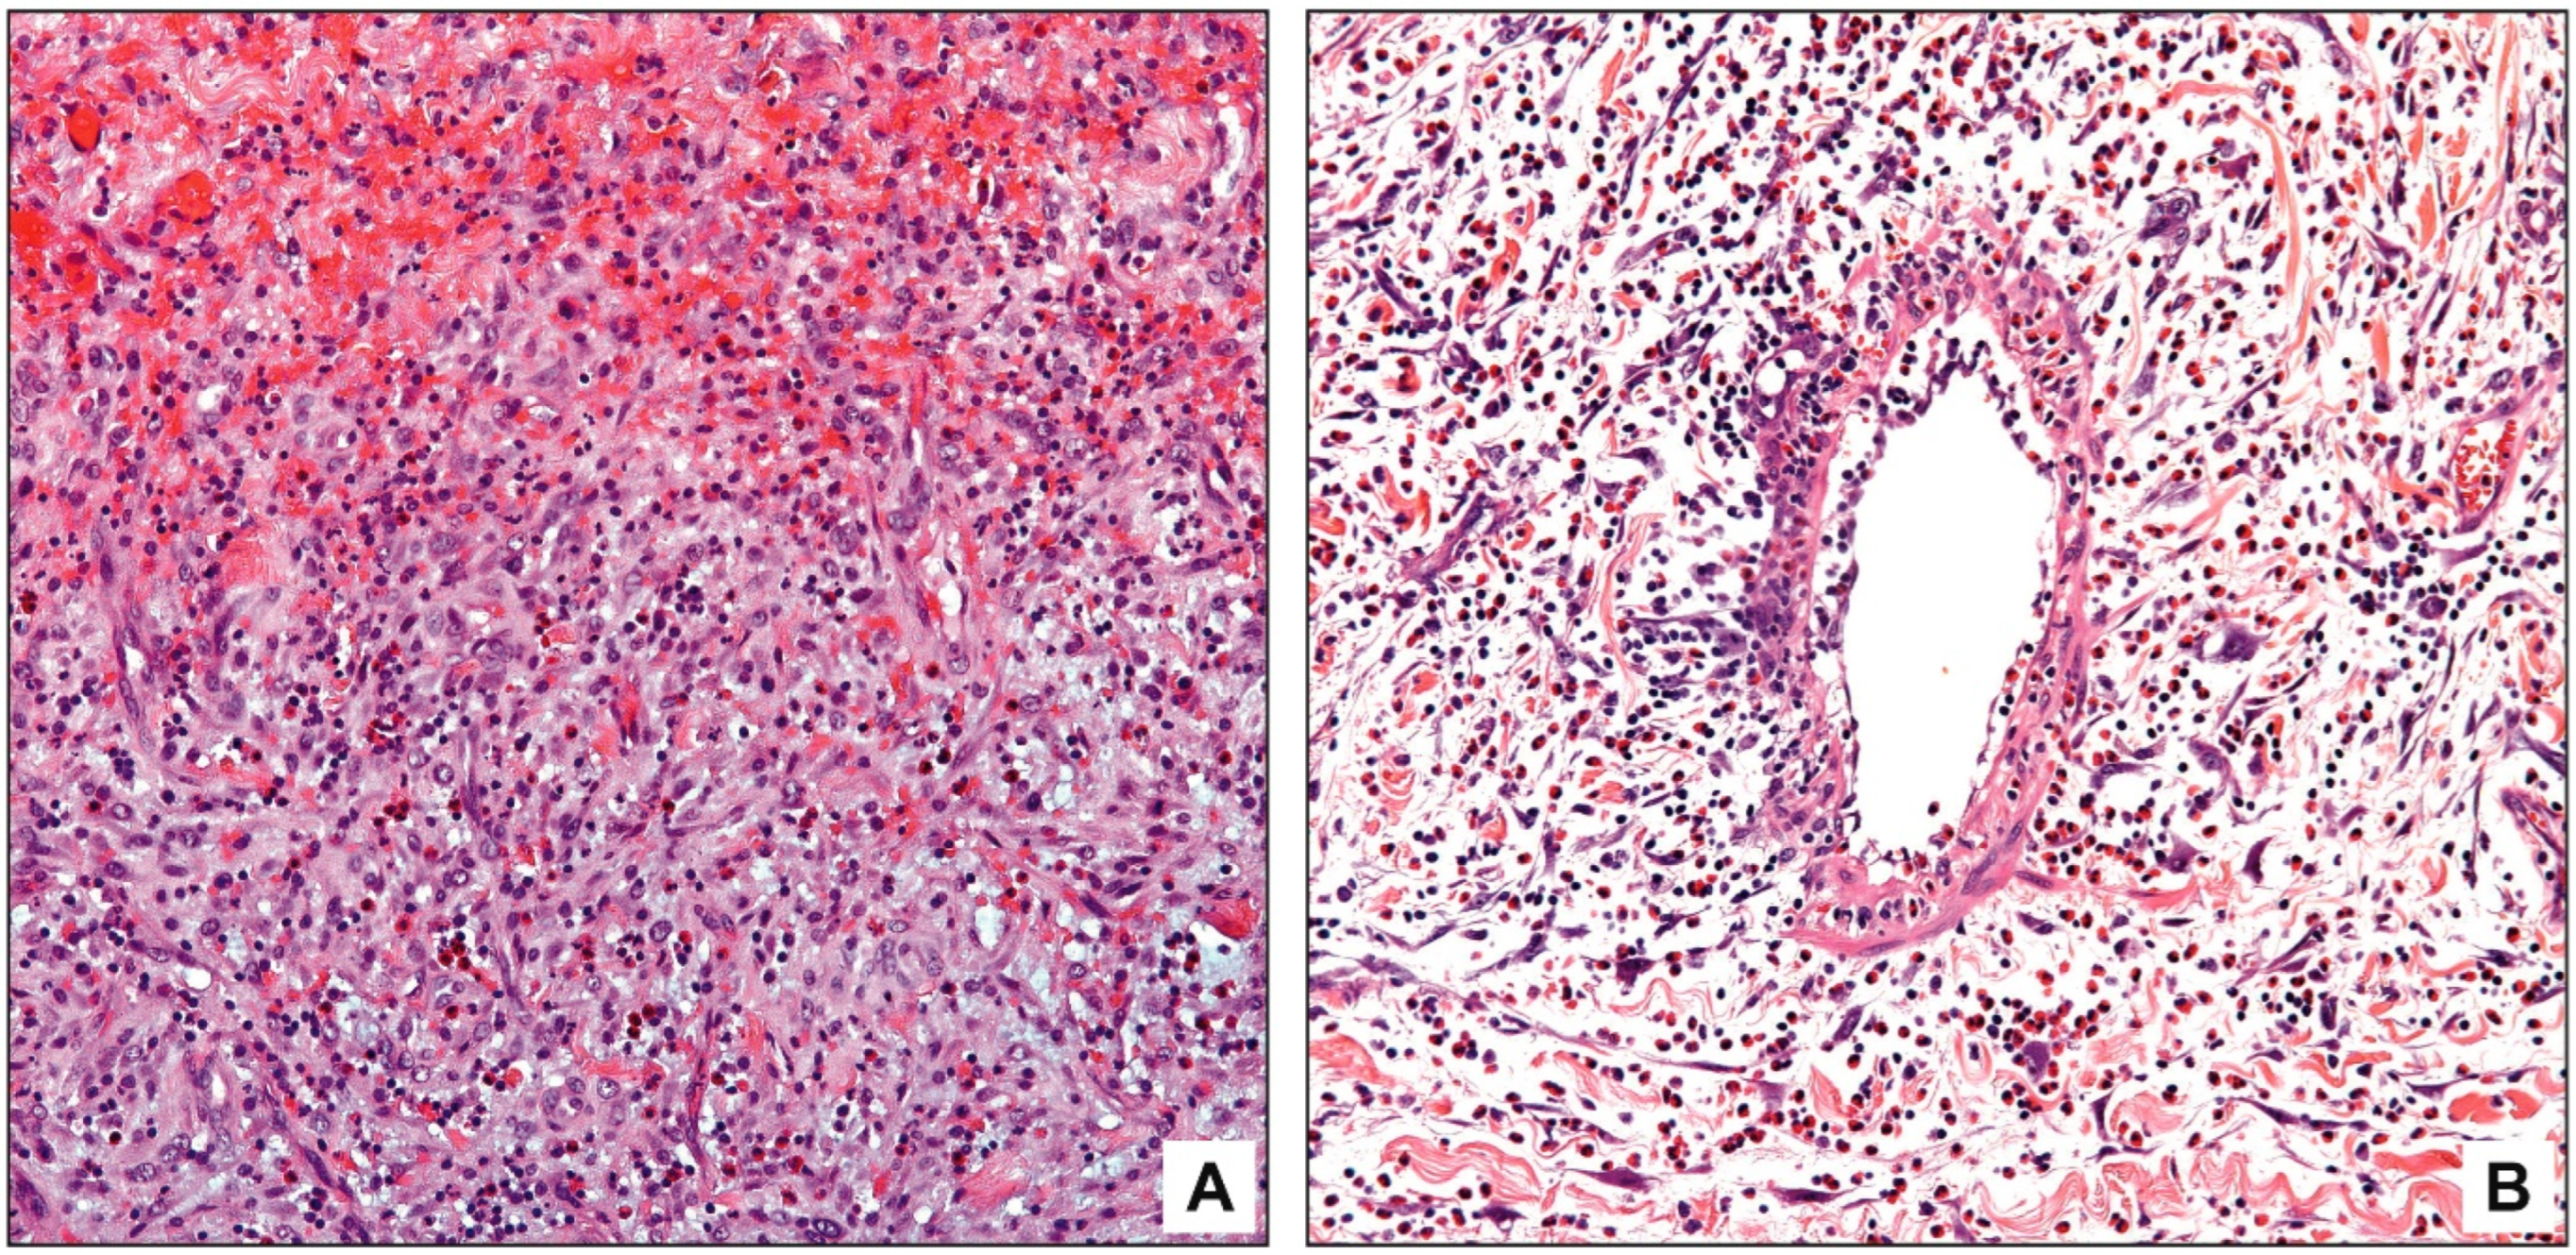

4. Discussion